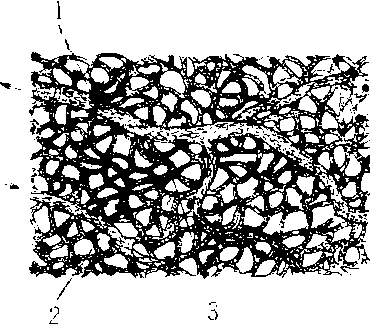

蛙足蹼内的微管网 1.小静脉 2.小动脉 3. 吻合(交通支) 毛细血管 毛细血管maoxixueguan又称微血管。分布于各种组织和细胞间的最微细的血管。平均直径7~9微米,数量极多,成网状分布。管壁主要由一层扁平梭形的内皮细胞构成。最细的毛细血管,一个内皮细胞可围成整个管壁,细胞基底面附着于外侧基膜上。内皮外有薄层结缔组织,含有外膜细胞。管壁外还紧贴有周细胞。毛细血管内皮细胞之间一般借少量细胞间质互相嵌合,在电镜下可见到有的内皮细胞具有窗孔,有的含有吞饮小泡。相邻的内皮细胞之间有较大的间隙或缝隙连接。有利于血液和组织之间的物质交换。特别是吞饮小泡对大分子物质的交换有重要意义。毛细血管壁具有极大的通透性,是管内血液与管外组织液进行物质交换的场所。 ☚ 静脉 动脉血和静脉血 ☛ 毛细血管capillary最细小的血管叫毛细血管。毛细血管仅由1层内皮细胞及外周薄层结缔组织构成,是管壁最薄、管腔最细的血管。平均直径7~9μm,一般可容1~2个红细胞通过。毛细血管彼此互相连接成网,在代谢比较旺盛的器官(如肾、肺),毛细血管网比较丰富;在代谢作用较低的平滑肌、腱等,毛细血管网比较稀疏。毛细血管对气体交换和物质代谢十分重要。 毛细血管位于动脉与静脉之间的极微细血管。数量很多,遍布全身各处,血管壁非常薄。有利于血液与组织和细胞之间进行氧及营养物质交换。 毛细血管 毛细血管分布于各器官的组织和细胞之间的最微细血管。其特点是口径细(平均约8~10微米)数量多、相互吻合成网。毛细血管壁很薄,通透性大,血流速度慢,是血液与组织液进行物质交换的场所,故称交换血管。毛细血管由一层扁平内皮细胞组成,有的内皮细胞具有窗孔,有的含有吞饮小泡,相邻内皮细胞之间有较大的间隙,这些特点均是毛细血管进行物质交换的形态学基础。血液内的氧气和营养物质经毛细血管渗入组织液,而细胞的代谢产物则渗入组织液经毛细血管进入血液,从而完成物质交换。 ☚ 静脉曲张 毛细血管的老化 ☛ 毛细血管capillary亦称真毛细血管。是由微动脉和后微动脉呈直角发出的许多分支。毛细血管口径细,数量多,总截面积大,血流速度慢,通透性大,是与组织液进行物质交换的场所,故又称交换血管。 毛细血管 毛细血管毛细血管是微动脉末端的分支,是最细的血管。它们长约20~100mm,内径5~10μm,分支多,互相通连成网。它们分布很广,除上皮、角膜、晶状体、玻璃体和软骨外,存在于其余的组织和器官中。毛细血管网的疏密程度反映它们所在的局部组织和细胞的代谢率和耗氧量。每平方毫米组织所含毛细血管的数目有显著差别,心肌约2000条,脑皮质1000条,骨胳肌600~1200条,皮肤和结缔组织约50条。 毛细血管的结构 它们的管壁很薄,由内皮、基板和少许结缔组织组成,后者包括胶原纤维、网状纤维和毛细血管周围细胞。 内皮 它们是一层梭形或不规则形的扁平细胞,厚约0.1~0.4μm。由1~3个细胞围成毛细血管的周径,细胞的长轴与血管长径一致。核扁长圆形,染色质颗粒细密,核仁不明显。胞质含一般的细胞器,但不丰富。在细胞连接附近和临腔面有少许细丝和粗丝,核周围常有直径10nm的中间丝。有证据表明,细胞受刺激时能收缩。内皮细胞的特殊结构是有质膜小泡和窗孔。质膜小泡也名吞饮小泡,由细胞游离面或基底面的细胞膜内凹所成,直径约60~70nm,内含水溶性物质。小泡形成后与细胞膜脱离,经胞质移向对面,与此面细胞膜融合,将内容物释放到细胞外。它们是输送大分子物质出入血管的运载工具。已知它们能输送直径大于2nm的分子。窗孔呈圆或卵圆形,是贯通细胞全厚的孔。细胞游离面和基底面的膜在孔缘相连。有些血管的窗孔有厚4~6nm的膜封闭,称隔膜。隔膜有复杂的微细结构,但其化学性质和意义所知很少。窗孔是物质通透的孔道,能透过30nm以下的分子。窗孔大小不一,在脉络丛和眼睫状体的直径约40~50nm,在内分泌腺的约30~50nm,在肝血窦和肾血管球的约100nm。它们的大小和数目与血管的通透性成正比。 内皮细胞游离面除有质膜小泡的开口和偶见短小的微绒毛外,大部分较平坦。此面覆盖厚约5~6nm的絮状膜,称内皮内层或毛细血管内层,与细胞衣性质相同。此层可分固定层和可变层。固定层成自唾液酸、细胞膜糖蛋白和糖脂的寡糖链,有识别经内皮细胞输送的物质的作用。可变层成自吸附的血浆蛋白,能保护内皮。 内皮细胞相邻面或重叠或互相嵌合,细胞间有10~20nm的细胞间隙,其中含低电子密度的均质物,为糖蛋白。细胞间有紧密连接,使细胞彼此牢固相连并封闭细胞间隙。毛细血管近微动脉段称动脉毛细血管,细胞间隙较窄,有紧密连接。毛细血管近微静脉段称静脉毛细血管,细胞间隙较宽,不见紧密连接。细胞间隙也是物质出入血管的重要通道,小于9nm的分子能通过。细胞间隙的宽度和细胞连接因生理和病理的因素而变。血管损伤,局部组胺或5-羟色胺增多,使间隙变宽,血管通透性变大。内皮细胞除有上述功能外,还有别的作用(参见“循环系统”条)。 基板 内皮细胞周围有厚约20~60nm的基板,其性质和构造与其他细胞的基板相似,是内皮细胞的产物。内皮细胞与基板间有窄隙,称内皮下间隙或血管周围间隙。它在静脉毛细血管最明显。刚透过内皮细胞的大分子物质,出血或炎症时逸出的血细胞等,都暂时停留于间隙中。基板大概有多方面的功能,它能保持毛细血管通畅,能使气体、水、脂溶性物质和10nm以下分子透过。此膜断裂或增厚都属病理变化。 毛细血管周围细胞 这是紧附于毛细血管周围的薄层结缔组织细胞的概称。常见以下几种细胞: ❶周细胞:也称内皮周围细胞或外膜细胞,呈扁长形并有长突起,纵向围绕内皮。电镜下,它们象未分化的细胞,核长圆并弯曲。线粒体不多,粗面内质网和滑面内质网短小,位于核两端,高尔基复合体不发达。胞质含少量微丝和微管,还有些吞饮小泡。周细胞外有基板围绕,并与内皮的基板相连。毛细血管的周细胞多少不等,脑的毛细血管周细胞较多,肾血管球、肝血窦、肺泡和肌肉的毛细血管没有周细胞。周细胞的性质和功能所知较少,它可能是未分化的间充质细胞,于炎症或创伤后血管再生时能分化为内皮细胞、成纤维细胞和血管平滑肌。周细胞没有收缩能力。 ❷外膜细胞:外膜细胞一词的涵义不一,有人指周细胞,也有人指沿毛细血管周围分布的成纤维细胞、巨噬细胞和未分化间充质细胞等。近年较趋于赞同后者的定义。周细胞与外膜细胞的区别是,前者紧贴血管外面,有基板包被; 后者散在于血管周围的结缔组织中。不同组织和器官的毛细血管所附的外膜细胞类型和多寡不等。肾血管球周围没有外膜细胞。 Rouget(1875)观察活体蛙眼瞬膜时,曾见具有长分支突起的细胞包围毛细血管,称Rouget细胞,它受刺激时能收缩。其后的研究表明,它们并无平滑肌细胞具有的双折光性,电镜下未见含肌丝或与收缩有关的结构。刺激哺乳类的毛细血管,发现其收缩性在于内皮细胞,而非Rouget细胞。现今一般认为Rouget细胞相当于哺乳类的周细胞,也有人认为它们相当于中间微动脉的平滑肌细胞。 毛细血管的类型 光镜下毛细血管的构造很相似,但管腔大小和形状不同。分布于某些内分泌腺、肝、脾和骨髓等的毛细血管腔大,形状不规则,称窦状毛细血管、血窦或窦状隙。电镜下,毛细血管的内皮细胞、基板和细胞连接等有明显差别,据此将毛细血管分三型: ❶连续毛细血管: 内皮细胞厚0.2~0.3μm,胞质含许多质膜小泡。细胞彼此紧密相连,细胞间隙宽10~20nm,常有紧密连接。基板完整,厚约20~50nm(图1)。在周细胞存在处,基板分开,包裹周细胞。此型血管分布于肌组织(平滑肌、骨胳肌和心肌)、结缔组织、中枢神经系、肺、皮肤、外分泌腺和生殖腺等器官; ❷有孔毛细血管:内皮细胞不含胞核的部分很薄,厚0.05~0.1μm,质膜小泡少,有数目不定的窗孔,孔上有或无隔膜封闭(图2)。细胞彼此相连较紧。基板完整。周细胞较少。此型血管存在于物质交换频繁的器官,如胃肠粘膜、某些内分泌腺、脉络丛、眼睫状体、肾血管球和肾小管周围。肾血管球内皮细胞有许多窗孔,孔没有隔膜封闭。脑垂体前叶、胰岛、肾上腺皮质、主动脉体等的有孔毛细血管腔大而不规则,相当于光镜下的窦状毛细血管; ❸不连续毛细血管: 相当于脾、肝和骨髓内的血窦或窦状隙。它们管腔大,很不规则,管径达30~40μm以上。内皮细胞有或没有窗孔。细胞相邻面多无紧密连接,细胞间隙宽可达数百毫微米。基板完整或不完整,有的甚至没有。周细胞偶见。此型血管有的物质交换活跃,如肝;有的血细胞频繁出入,如脾和骨髓(参见“肝”、“脾”和“骨髓”条)。

图1 连续毛细血管 1.细胞连接 2.基板 3.内皮细胞 4.周细胞